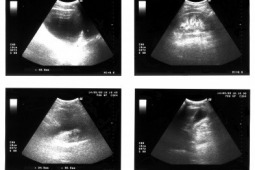

Terminem cholangiocarcinoma określa się wewnątrzwątrobowe, okołownękowe (guz Klatskina) oraz zewnątrzwątrobowe guzy dróg żółciowych. Objawy zależą od lokalizacji guza, rozległości naciekania oraz od stopnia zwężenia dróg żółciowych. Diagnostyka obrazowa jest podstawowym sposobem oceny zaawansowania nowotworów dróg żółciowych. Postęp techniczny nowoczesnych metod obrazowania, głównie ultrasonografii, tomografii komputerowej i rezonansu magnetycznego, spowodował, że wcześniejsze ustalenie rozpoznania raka jest możliwe, jeśli pacjent zostanie skierowany na badanie w odpowiednim momencie.